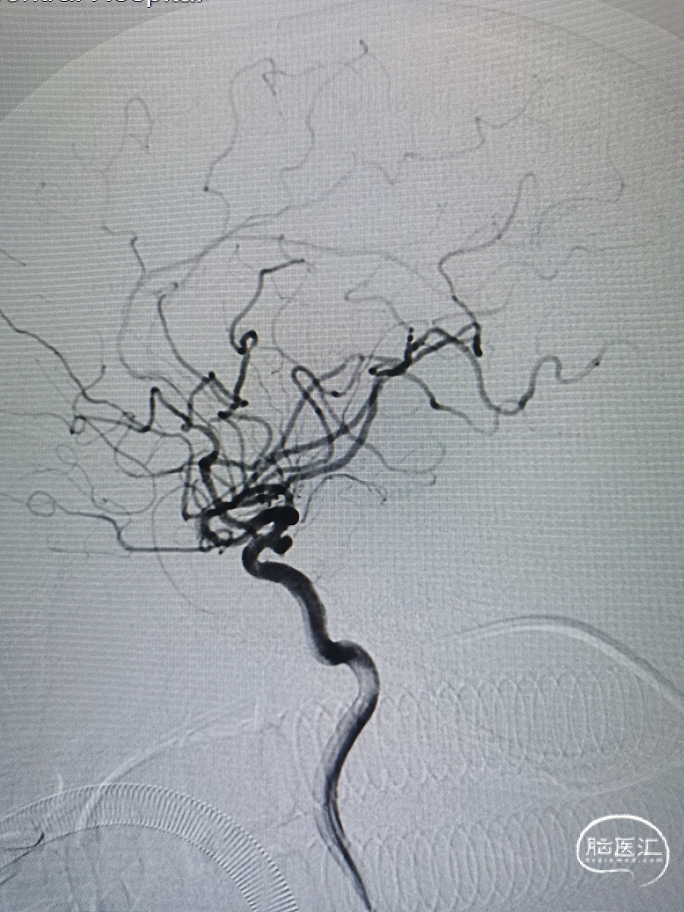

CTA:右侧颈内动脉后交通段动脉瘤。

DSA:右侧颈内动脉后交通段动脉瘤,动脉瘤大小约:3.5mm×2.2mm,瘤颈宽约3mm,为宽颈动脉瘤。

透视下弹簧圈填塞已勾勒出动脉瘤轮廓,支架位置良好,完全覆盖瘤颈,Catalyst 7中间导管全程稳定支撑。

标准正侧位造影,动脉瘤不显影。

3D造影,动脉瘤不显影。